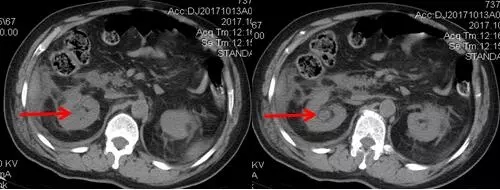

術(shù)后CT,箭頭所指為腎結(jié)石被徹底清除

三日后,曾奶奶病情逐漸穩(wěn)定,各項感染指標(biāo)逐漸恢復(fù)正常,復(fù)查CT顯示腎結(jié)石已經(jīng)被完全清除,現(xiàn)已康復(fù)出院。就此,困擾曾奶奶多年,反復(fù)感染差點致命的腎結(jié)石頑疾被徹底治愈。曾奶奶全家人對于愛康醫(yī)院泌尿外科專家高超的碎石取石手術(shù)技藝更是贊許有加,對泌尿外科團隊的工作給予衷心感謝和高度評價。